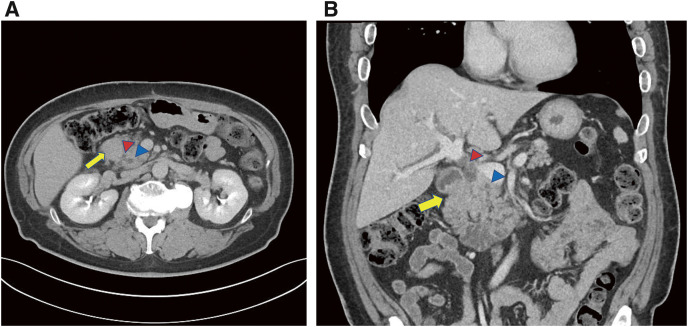

Case presentation: A 53-year-old man was admitted with abdominal distension and recurrent vomiting. Esophagogastroduodenoscopy revealed a complete duodenal obstruction without malignant findings. Computed tomography revealed wall thickening in the second portion of the duodenum. The common bile duct and main pancreatic duct were not dilated. As there was no evidence of malignancy, we performed gastrojejunostomy as a bypass to improve the symptoms. Five months later, follow-up blood examinations showed elevated total bilirubin levels, and computed tomography revealed persistent thickening of the duodenal wall with exacerbated dilation of common bile duct and main pancreatic duct. Mucosal biopsies from the oral and anal sides of the stenosis revealed no malignancy. Due to a strong suspicion of malignant disease and difficulty in preoperative biliary drainage, we performed pancreatoduodenectomy. Pathological examination revealed mucinous adenocarcinoma with submucosal and subserosal invasion of the duodenum. We finally diagnosed this case as ampullary carcinoma.